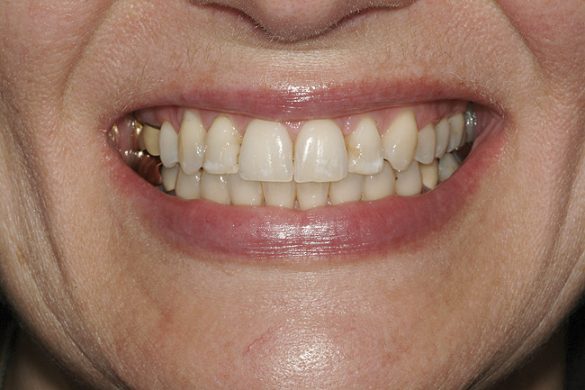

O pacientă în vârstă de 44 de ani s-a prezentat pentru evaluarea şi îmbunătăţirea zâmbetului ei. Acuza principală era reprezentată de afişarea neatractivă a coroanelor posterioare din aur, asociată cu petele albe inestetice de pe dinţii frontali (fig. 1, 2). Scopul ei convingător pentru solicitarea tratamentului a fost acela de a dobândi un „zâmbet deosebit”.

DENTO-FACIAL: Evaluarea zâmbetului pacientei a evidenţiat o dinamică labială maxilară medie şi afişarea ţesuturilor la zâmbire (fig. 2). Nivelurile gingivale maxilare inegale, exostoza osoasă vestibulară vizibilă corespunzător 1.6., dinţii rotaţi sau malpoziţionaţi, coloraţia de pe mai mulţi dinţi frontali, o „linie a surâsului inversată” , asimetria dentară şi un plan ocluzal maxilar neregulat reprezentau puncte semnificative în cadrul evaluării dentofaciale. Dorinţa pacientei de a avea un zâmbet ideal sau „generat de media” a accentuat dificultatea cazului. Dinamica labială maxilară medie şi afişarea în consecinţă a ţesuturilor a dictat evaluarea riscului pentru acest caz.